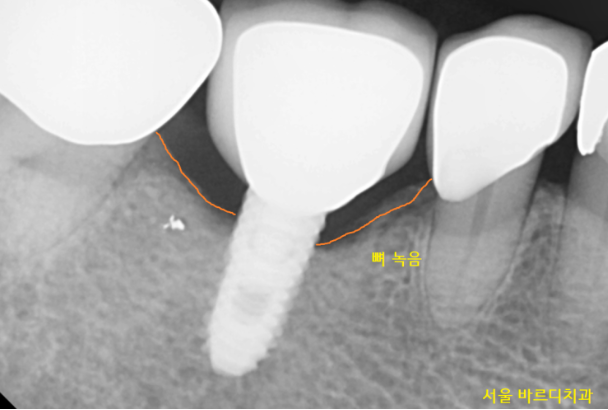

임플란트 주변 염증으로 인하여

잇몸 뼈가 녹아있었습니다.

아직 관리하시면서 쓰실 수 있는 상황이라

(뽑을 정도는 아니라는거죠~)

풍산동 치과에서 잇몸 치료를 진행해 드렸는데요.

임플란트 염증으로 잇몸뼈가 많이 녹았습니다.

4년 전과 비교해 보면 잇몸뼈가 더 많이 녹은 것이

보이실 겁니다.